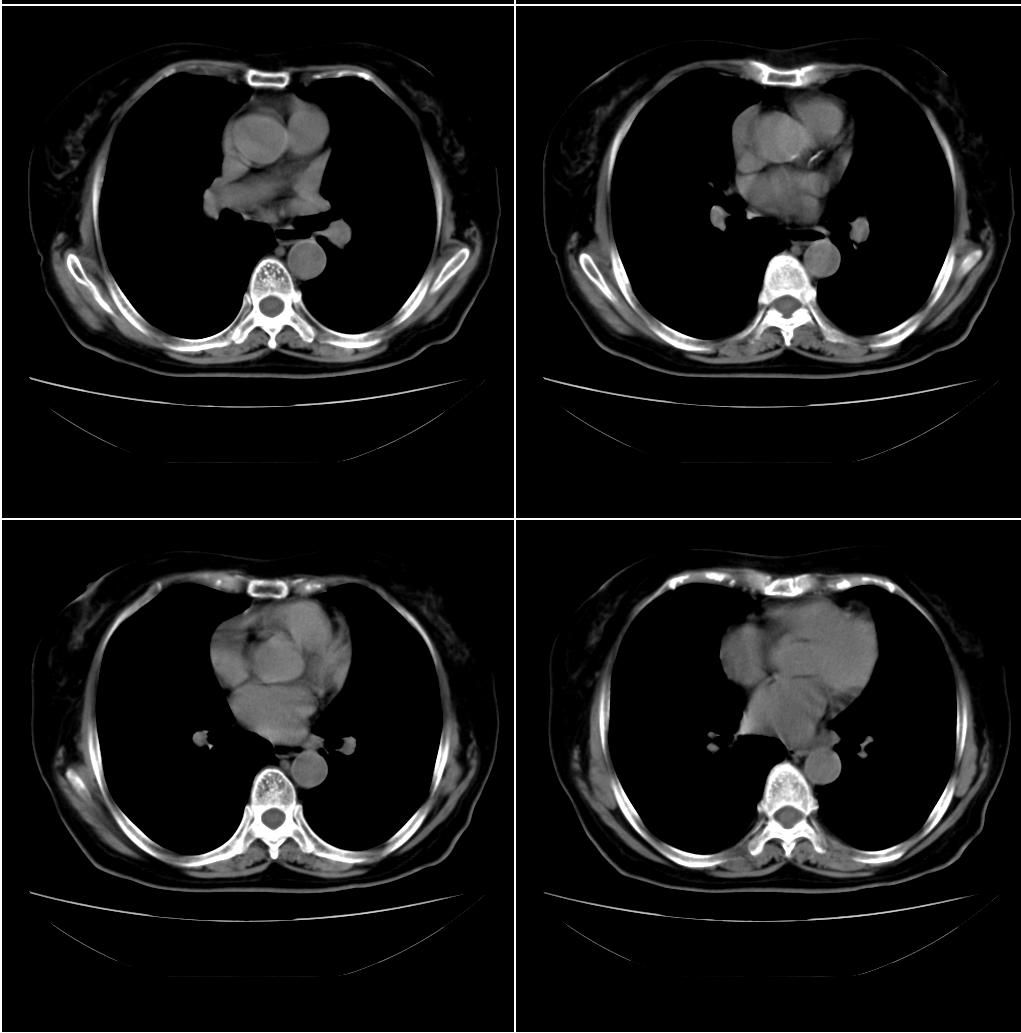

以下是引用zhangxu5888在2007-12-22 20:56:00的发言:[br]食道病变???纵隔淋巴瘤?

以下是引用卜一在2007-12-22 22:44:00的发言:[br]纵隔占位,支持:气管源性肿瘤!

以下是引用sxlcbc在2007-12-23 4:27:00的发言:[br]气管源性肿瘤觉得有点不靠谱啊,看上去气管是受压改变的。更像是上段食管的改变,周围淋巴结肿大,食管受压。看看以下六幅图片:[br]不过,有一点不好理解:食管肿瘤应该有食道症状的,再说食管癌出现周围这么大的淋巴结也不多见啊,如果考虑淋巴瘤倒是更合理一点,这样气管,食管受压改变也许更合理一些。[br][br]